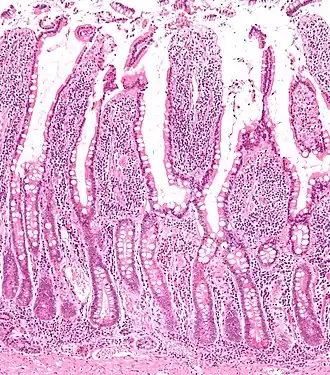

Micrograph of the small intestine mucosa showing the intestinal villi and crypts of Lieberkühn.

The three sections of the small intestine look similar to each other at a microscopic level, but there are some important differences. The parts of the intestine are as follows: